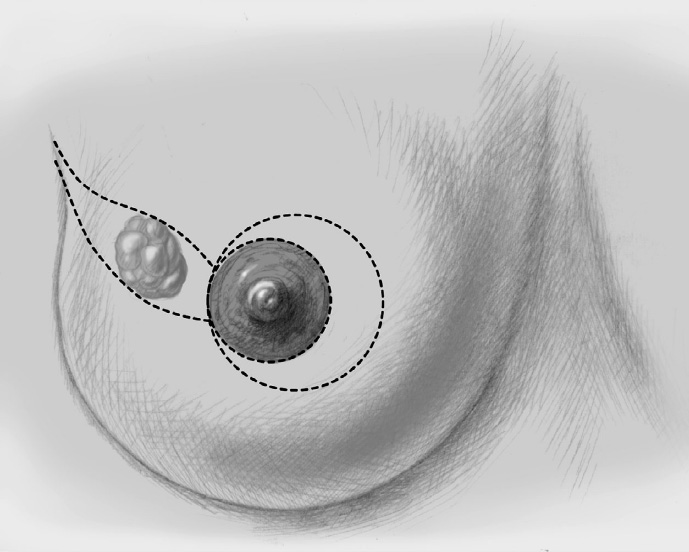

The incision line is drawn with the patient standing or sitting up, either the day before or immediately prior to operation.

The basic decision on whether to use a complex oncoplastic technique is made when the skin is marked preoperatively, with the patient standing or sitting upright. Many surgeons successfully combine the B-plasty incision with periareolar de-epithelialization and excision of a straight or curved ellipse of peripheral skin (Chapter 1.3). When marking the periareolar deepithelialization pattern, an eccentric incision may be necessary to adjust the repositioning of the nipple–areola complex to the anticipated volume displacement.

Segmental excision of the area containing the tumor with resection margins as wide as possible to meet oncological criteria. Oncoplastic techniques should be used to achieve maximal oncological safety and avoid subsequent further resection.

The incision is marked preoperatively with the patient standing, the day before the operation or immediately prior to operation, checking that the correct side is marked.

The incision is marked on the day before the operation or immediately prior to the operation with the patient standing.

The incision is usually the classic McKissock one, finally resulting in an inverted T scar, though the inferior pedicle (which will be de-epithelialized) is kept somewhat broader (as a guide, the scalpel shaft length is approximately 8–10 cm), because this bears and supplies the nipple–areola complex without an additional superior pedicle.

Marking the incision line is particularly difficult as gathering the skin along the vertical axis (midclavicular line) determines the ultimate breast contour. The new nipple–areola complex cannot be planned as exactly preoperatively as with an inferior central pedicle. The incision is usually periareolar and vertical (or perivertical). The subsequent operation, with slight variants, is also known as the LeJour technique and becomes the Marchac technique if it is extended to a small inverted T.

The nipple is repositioned at the most cranial point of the measured periareolar de-epithelialization area. If nipple repositioning over a long distance is necessary, a domelike extension in a cranial direction can be de-epithelialized beyond the purely periareolar de-epithelialization area (LeJour technique).

The first step after marking the incision line is periareolar de-epithelialization.